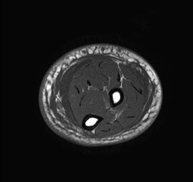

Exploració ideal per estudiar les lesions en músculs isquiotibials i quàdriceps, sovint lesionats en esportistes. També permet una bona valoració de tendons i de nervis perifèrics. La durada aproximada és de 20 minuts. No utilitza radiació ionitzan. - RM de Genoll

Exploració per estudiar lesions a l'articulació, com trencaments dels meniscals i dels lligaments creuats (únicament es poden detectar amb aquesta prova), condropatia o desgast del cartílag i moltes altres alteracions derivades de l'activitat esportiva i dels canvis degeneratius (osteoartrosi). La durada aproximada és de 18 minuts. No utilitza radiació ionitzant. - RM de Cama